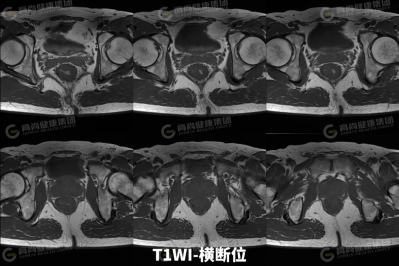

【高尚病例】直肠癌 MRI 评估与 TNM 分期